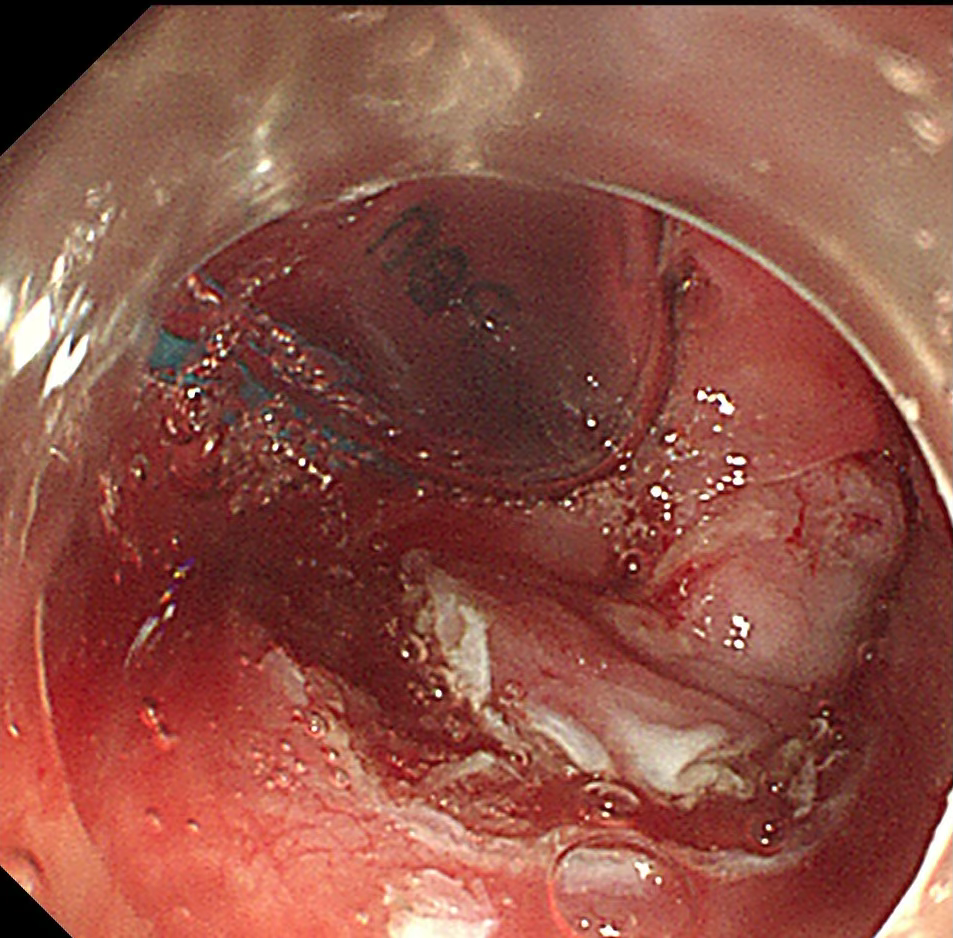

食管病灶

1.(食管33处)食管糜烂型鳞状细胞癌,Ⅱ级,肿瘤大小0.6×0.3cm,癌组织局限于黏膜内(M2);淋巴管及血管内未见癌栓;送检组织四周及基底部切缘未见癌组织。免疫组化结果显示:CD34(未见癌栓),D2-40(未见癌栓),Desmin(平滑肌+),E-cadherin(+),Ki-67(index≈40%),P53(+,突变型)。